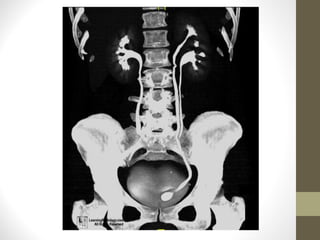

Anatomical landmarks

• Ureter

•

Emerge at hilum

Posterior to vein and artery

Lie at tips of transverse processes of vertebral bodies

Crosses pelvic brim on SI joint and runs forwards at lower end of

SIJ

• Lie anterior to the bifurcation of the common iliac vessels

• Run alongside internal iliac artery

• Run into tunnel of detrussor muscle to OU at lateral aspect of the

trigone

Anatomical landmarks • Ureter • • • • Emergeat hilum Posterior to vein and artery Lie at tips of transverse processes of vertebral bodies Crosses pelvic brim on SI joint and runs forwards at lower end of SIJ • Lie anterior to the bifurcation of the common iliac vessels • Run alongside internal iliac artery • Run into tunnel of detrussor muscle to OU at lateral aspect of the trigone